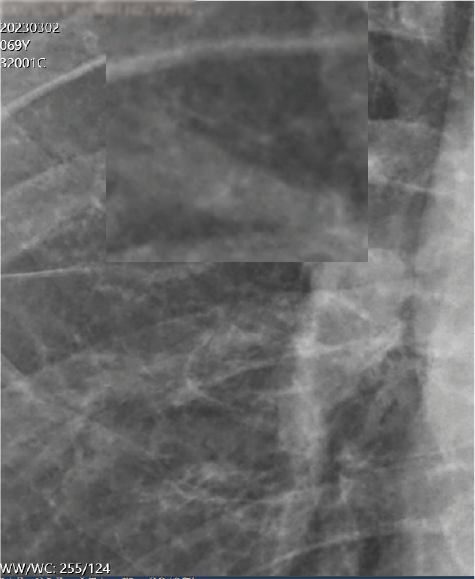

施打外泌體後

1.兩肺纖維化改善

2.左肺門附近結節變小

3.血氧濃度 >95%